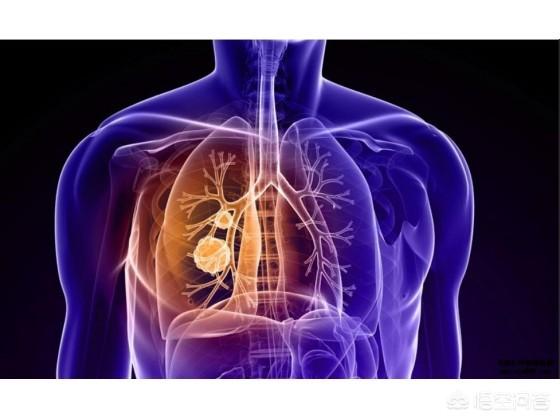

このテーマはかなり重いが、多くの肺がん患者とその家族が直面しなければならないことである。肺がんの罹患率、死亡率は悪性腫瘍の中で第1位であり、治療法も比較的多くなってきているが、その効果は決して楽観できるものではない。すべての治療が効果的でなく、患者の体調が徐々に悪化すると、生命を脅かすさまざまな事態が発生する。肺がんに限らず、実際、すべてのがん患者は、最終的にはがんそのものではなく、多臓器不全で死亡する。

肺がん患者の死亡は、以下のような原因によって引き起こされる可能性がある。

1.呼吸不全は、一般に患者の空気不足として知られ、進行肺癌患者に最も多い。中枢性肺癌では気管や主気管支が閉塞して空気が入りにくくなり、肺の無気肺が大きくなると、次第に息切れや呼吸困難に悩まされるようになる。胸膜転移により大量の胸水が貯留し、肺組織が圧迫されて肺が再開通できなくなる患者もいる。また、肺病変が多すぎて有効呼吸膜面積が著しく減少している患者もいる。これらの理由はすべて、最終的に胸部圧迫感、息切れ、座位呼吸を引き起こし、最終的には呼吸不全に至る。

国立がんセンターが発表したデータによると、2015年、中国でのがん死亡者数は約233万8000人で、そのうちの1割が死亡している。肺がんによる死亡者数は631,000人で、これは人口10万人のうちおよそ45.8人が肺がんで死亡することを意味する。肺がんの予防と制御は、がんとの闘いの重要な部分である。

肺がん患者は通常どのように亡くなるのか?

1.最も多いのは呼吸不全

人間は、肺の空気交換機能に頼って酸素呼吸を行い、地球上で生存している。肺不全は、巨大な腫瘍、大量の胸水、広範な肺転移、気道閉塞などの進行した肺がんによって引き起こされることが多い。

WHOのデータによると、肺がんは年間罹患数、年間死亡数ともに世界第1位で、罹患率はますます高くなっている。

肺がんの死因は何ですか?

1.臓器不全

進行した肺がんの多くは、肝臓、脳、骨に転移し、臓器不全に至ることがある。